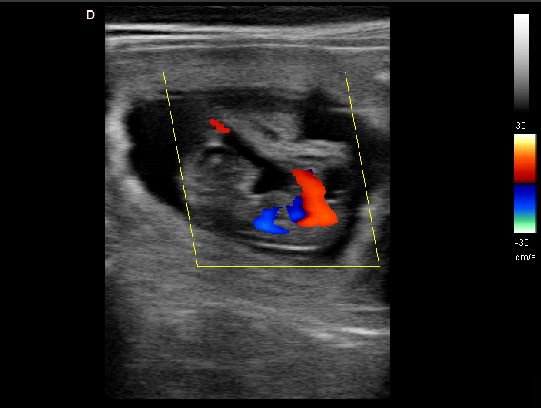

心臟超聲檢查:

心臟超聲是唯一能動(dòng)態(tài)顯示心腔內(nèi)結(jié)構(gòu)、心臟的搏動(dòng)和血液流動(dòng)的儀器,對(duì)人體沒(méi)有任何損傷。心臟的各個(gè)結(jié)構(gòu)清晰地顯示在屏幕上。通過(guò)彩超的測(cè)量,醫(yī)生可了解瓣膜病變的程度以決定保守治療還是手術(shù)治療。心肌的增厚、心腔的擴(kuò)大都要依賴彩超來(lái)判斷;對(duì)冠心病,彩超能直觀顯示心肌的運(yùn)動(dòng)狀況及心功能,向臨床醫(yī)生提示心肌缺血的部位。